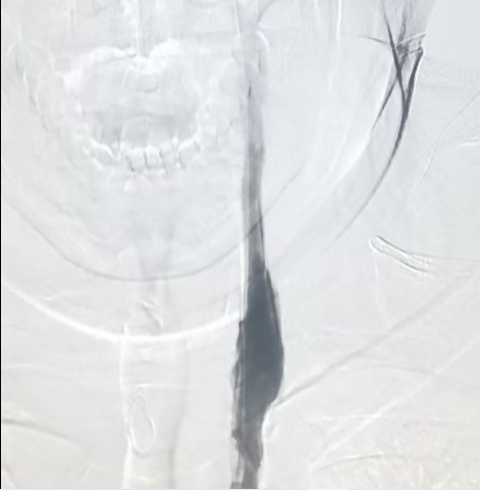

术前OCT:颈动脉内大量血栓,伴有部分破溃,并伴有局部管腔狭窄

术后OCT:左侧颈动脉血管管腔狭窄明显改善,支架管壁伴有局部血栓,少量组织脱垂。

术前OCT示血管管腔狭窄,内可见脂质斑块

术后OCT示支架近远贴壁良好,管腔狭窄明显改善。